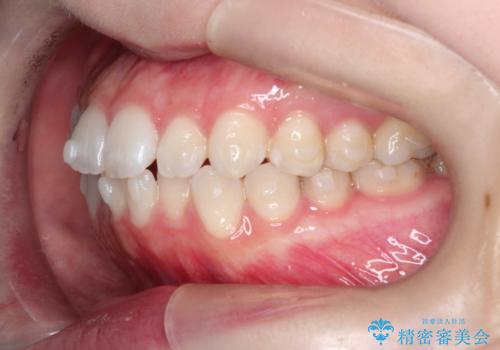

【インビザライン】がたつきをなおしたい

- 上下の前歯の凸凹が気になり、来院されました。

インビザラインで綺麗に仕上がり、満足していただきました。